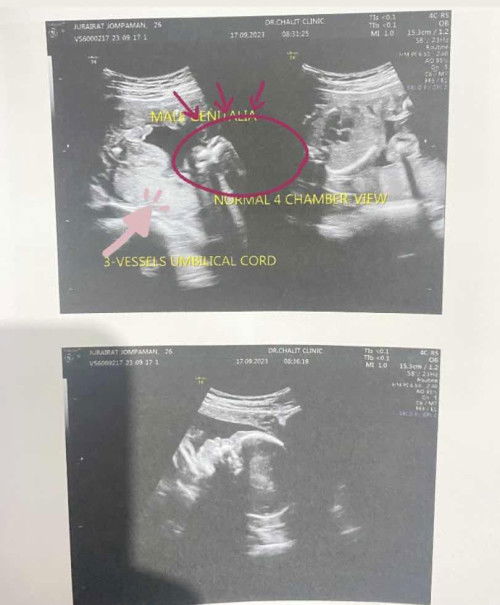

แม่แม่ช่วยพิจารณาทีค่ะว่าเพศชายจริงๆหรอคะ

แม่เข้าใจว่าที่วงกลมสีแดงคือหัวลูกศรชี้ลำตัว ขาและเท้า หมอบอกแม่แม่ว่าได้เพศชาย แม่งงเลยถามหมอว่าดูจากตรงไหนคะ หมอแจ้งว่าให้แม่ดูที่ปลายขาตัวM แม่มีวิดีโอที่ถ่ายไว้ตอนหมอซาวด์ให้พอจิ้มท้องแม่ปุ๊ปหมอแจ้งว่าเพศชายเลย แม่เลยงงๆว่าเดี๋ยวนะมันไม่ใช่หัวลำตัวแล้วเท้าหรอ ช่วยพิจารณาหน่อยค่ะ คือหมอก็ซาวด์ไวมากจิ้มปุ๊ปบอกปั๊บปริ้นรูปตรวจเสร็จเลย😂😂#ขอคำแนะนำหน่อยค่ะ #ขอบคุณสำหรับคำตอบค่ะ